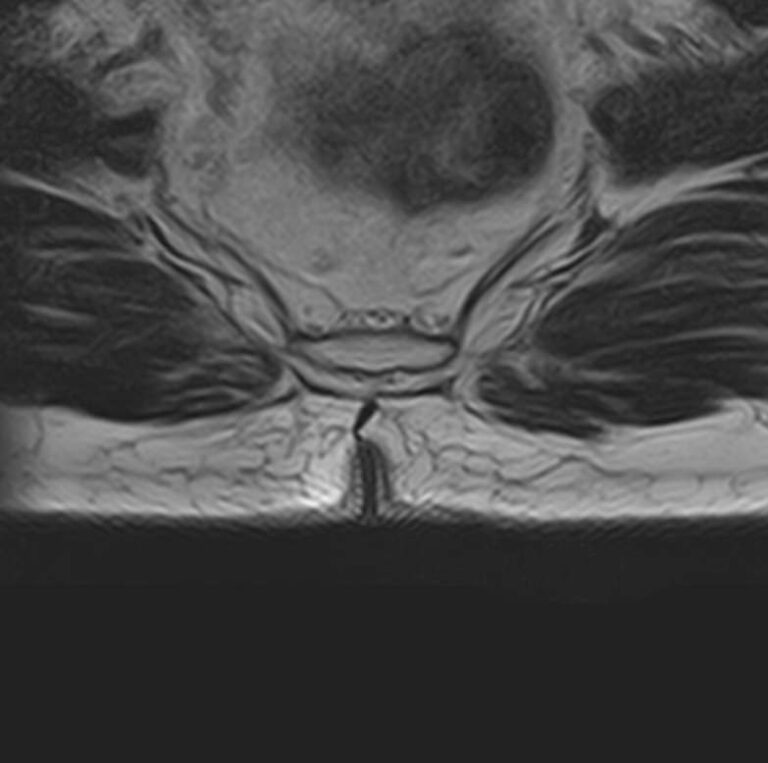

Магнитно-резонансная томография копчика является высокоинформативным методом выявления причин возникновения кокцигодинии. В клинике «Доступная медицина» диагностика осуществляется на новейшем высокопольном томографе закрытого типа TOSHIBA VANTAGE TITAN 1,5 Тесла, обеспечивающем высочайшее качество изображений исследуемой зоны.

Томограф позволяет детально визуализировать как костные структуры копчика, так и окружающие мягкие ткани данной анатомической области, включая мышцы, связки, нервные сплетение, сосуды и прилежащие органы малого таза. МРТ копчика дает возможность диагностировать патологические процессы в самом копчике и выявить их взаимосвязь с патологией окружающих структур.